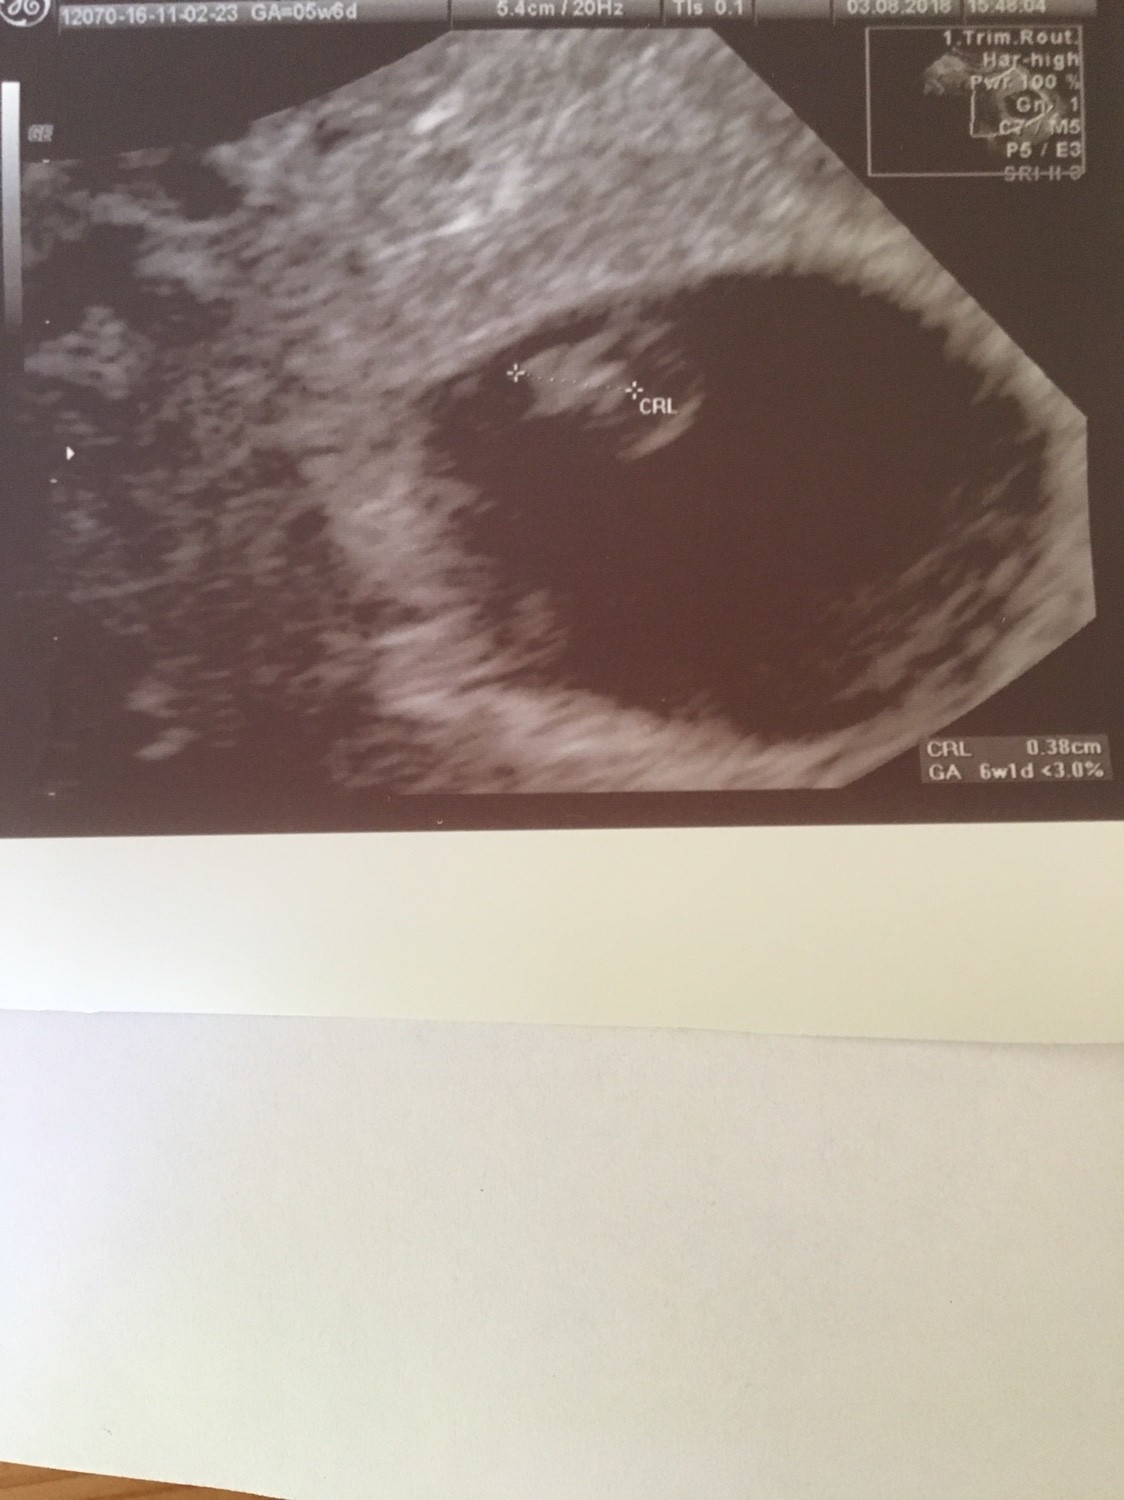

Ja już po wizycie. Wszystko dobrze. Serduszko bije [emoji173]️. CRL 0.38cm. Według OM dzisiaj mam 5t6d, a według usg 6t1d. Poród na 30.03, ale zostaje z Wami jeśli mogę. Zobacz załącznik 884619